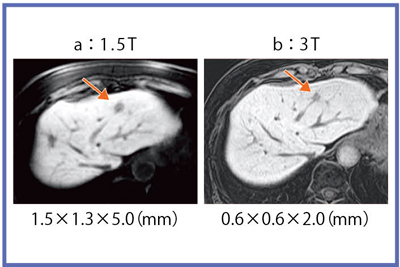

3Tでは,0.6mm×0.6mm×2.0mmのボクセルサイズで,非常に高分解能の画像を得ることができ(図10),造影画像や,MRCPでも高精細に描出可能である。一方,画像枚数が膨大になるため,ルーチン化にあたって読影時間やPACS容量が問題となり,これらをどのように克服し臨床応用していくかが今後の課題と言える。

図10 HCC症例:Gd-EOB肝細胞相の高分解能画像

3Tでは腫瘍辺縁が明瞭に描出されている。